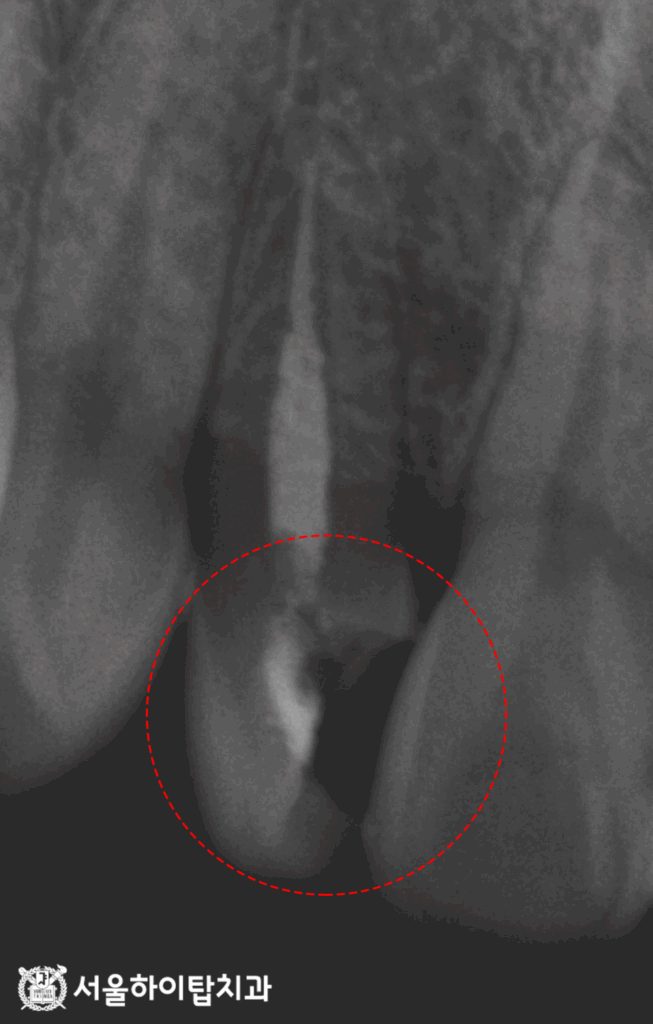

3. 재신경치료

먼저, 채워져 있던 충전재를 제거하여

내부를 깨끗하게 만들고,

정밀하게 세척, 소독합니다.

이후 근관의 형태에 맞게

가타퍼차(Gutta-percha)의

마스터 콘(Master cone)을 먼저 넣어

적합 여부를 확인합니다.

X-ray를 통해 이 마스터 콘이

뿌리 끝까지 도달했는지 확인하는데,

주안역 치과 에서 이는 이후

근관 전체를 빈틈 없이 밀봉하기 위한

기준이 된다고 설명해 드립니다.